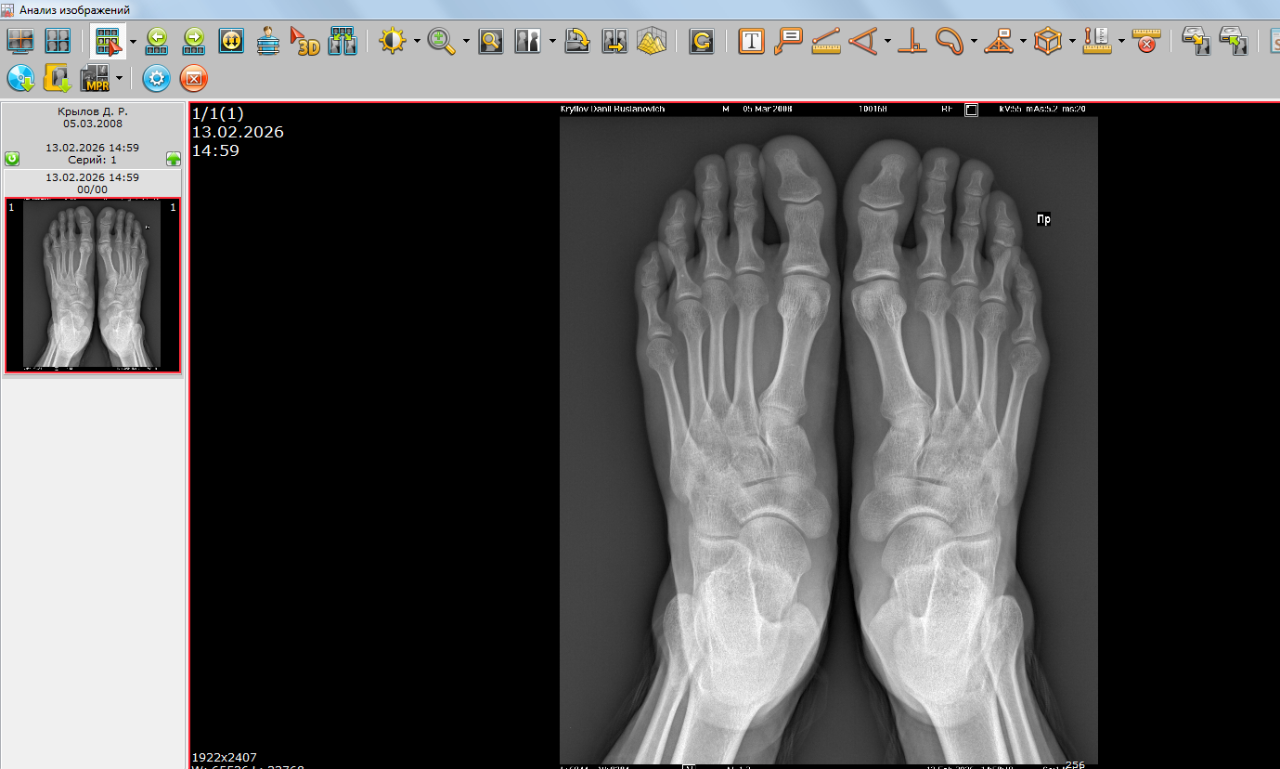

Открыты ли зоны роста на данных снимках

Здравствуйте, можно ли по данным снимкам определить открыты ли зоны роста? А также совпадает ли костный возраст с паспортным? Мой рост 174 см, Рост отца 176 см, рост мамы 158см. За год вырос на 3 см. Заранее спасибо.